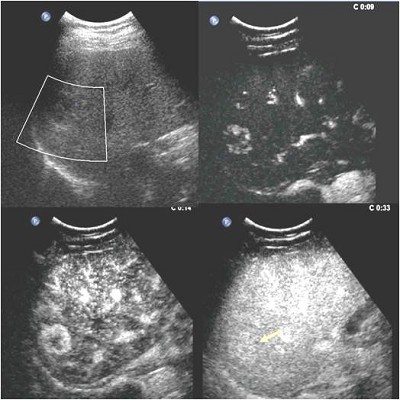

图1

图1和图2分别为两例肝脏占位性病变,仅凭二维和彩色多普勒超声无法定性,分别作了超声造影检查,根据病灶增强模式等超声造影特点,诊断出图1中的病灶为良性的血管瘤,临床上观察即可,而图2中的病灶为肝细胞癌,临床需要手术等治疗。